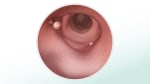

Procedures that can look inside the colon and find polyps include colonoscopy, flexible sigmoidoscopy, and CT colonography (virtual colonoscopy). Polyps found during a colonoscopy can often be removed during the test. If polyps are found during one of the other procedures, you may need a colonoscopy.